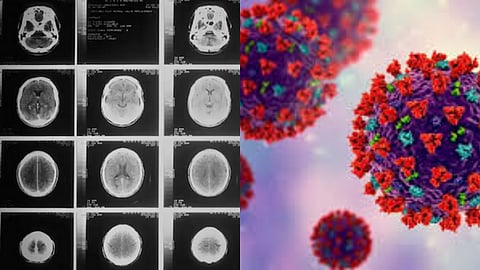

கொரோனா பெருந்தொற்றால் முதிர்ச்சி அடையும் மனிதர்களின் மூளை.. ஆய்வில் அதிர்ச்சி..!

கொரோனா பெருந்தொற்றால், மனிதர்களின் மூளை வழக்கத்தை விட ஆறு மாதங்கள் முதிர்ச்சி அடைந்துள்ளதாக புதிய ஆய்வில் தெரியவந்துள்ளது. இங்கிலாந்திலுள்ள நாட்டிங்ஹாம் பல்கலைக்கழக (Nottingham University) ஆராய்ச்சியாளர்கள் நடத்திய ஆய்வில், கொரோனாவால் பாதிக்கப்பட்டவர்கள் மட்டுமல்லாமல், பாதிக்கப்படாதவர்களின் மூளையின் செயல்பாடுகளும் கூட வேகமாக வயதாகியிருப்பதை கண்டறிந்துள்ளனர்..கொரோனா ஊரடங்கு காலத்தில் மக்கள் சந்தித்த சமூக விலகல், தனிமை, தொடர்ச்சியான மன அழுத்தம் மற்றும் ஒழுங்கற்ற வாழ்க்கை முறையும் மூளையின் செயல்பாடுகளை பெரிய அளவில் பாதித்துள்ளதாக ஆய்வில் தெரிவிக்கப்பட்டுள்ளது.

இரண்டு ஸ்கேன்கள் எடுத்த 996 பங்கேற்பாளர்களின் தரவையும் ஆராய்ச்சியாளர்கள் பகுப்பாய்வு செய்தனர், இரண்டாவது ஸ்கேன் முதல் ஸ்கேன் செய்யப்பட்டதற்கு சராசரியாக 2.3 ஆண்டுகளுக்குப் பிறகு எடுக்கப்பட்டது. சில பங்கேற்பாளர்கள் தொற்றுநோய்க்கு முன்பு இரண்டு ஸ்கேன்களையும் செய்தனர், மேலும் சிலருக்கு தொற்றுநோய் தொடங்கிய பிறகு இரண்டாவது ஸ்கேன் செய்யப்பட்டது. இந்தத் தரவுகள் அனைத்தும் சேர்ந்து, மூளையில் ஏற்படும் மாற்றங்களைப் படிக்க AI மாதிரிக்கு உதவியது.